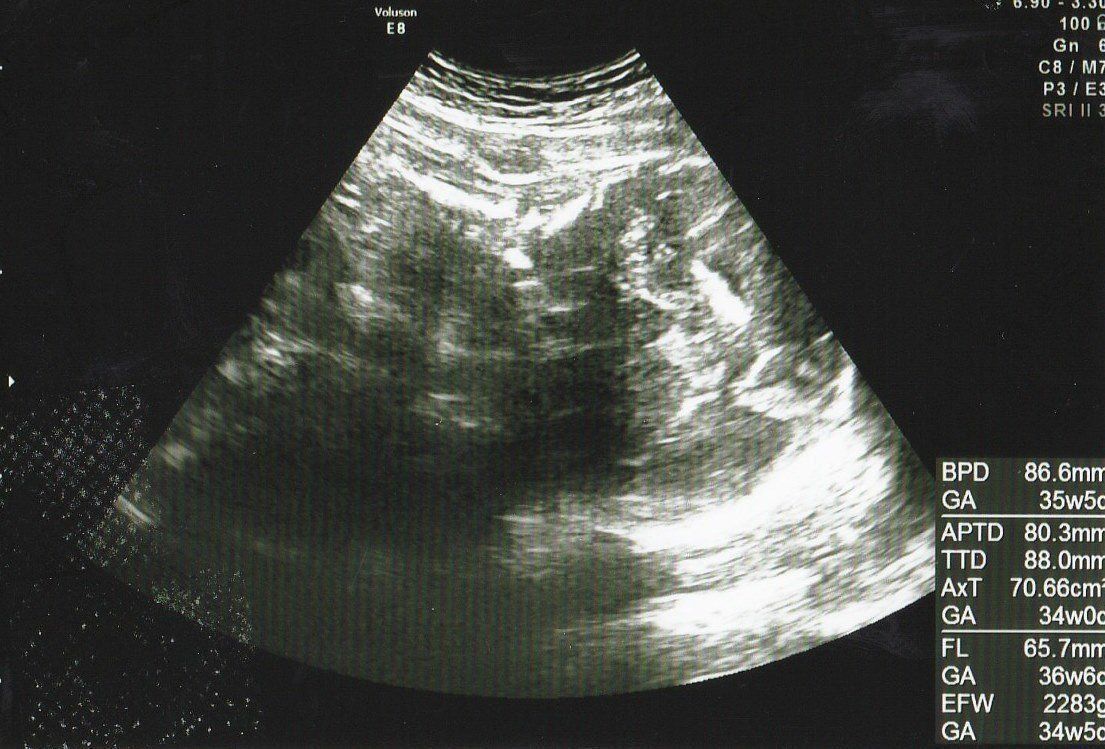

妊娠32週目のエコー写真 おなかがパンパンで苦しい毎日

推定体重=2283g

背中を向けているエコー画像です。赤ちゃんが大きくなってくると、素人の私の目ではエコー画像に写っているのが体のどの部分なのか、全くわからなくなってきました。エコーでみてもらうときに「右側が頭」「背中を向けている」など教えてもらい、「このゴツゴツしたのが頭か」なんて帰るのですが、当たり前ですがいつのまにか位置が変わっていて、最後までどっち向きでいるのかは自分ではわかりませんでした。

妊娠9ヶ月に入り、お仕事は一休み。低血圧で時々めまいがするようになりました。自分でどういう状態だとめまいが起きるかをわかるまでは、頻繁にめまいがして大変でしたが、コツをつかんでからは防ぐことができました。